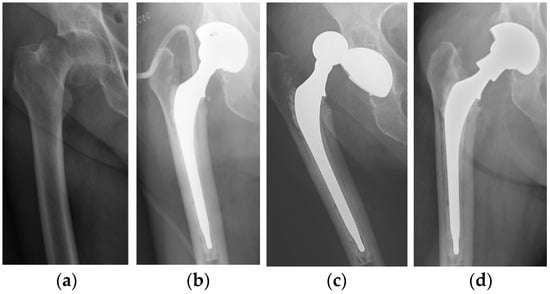

No dislocation occurred in the DMC group, while two dislocations were observed in the SC group. Both dislocations occurred during the first month after surgery: one in a male patient following an accidental fall and one in a female patient without any traumatic event. The first patient was treated with closed reduction and THA dislocation never recurred. The female patient suffered of postoperative moderate-grade delirium with poor cooperation in the rehabilitation program; dislocation occurred twice in the rehabilitation institute. In consideration of her mental state and poor compliance, she underwent a revision procedure: the femoral stem and acetabular cup were retained, the liner and the head were substituted and a neck adapter (Bioball®, Merete GmbH, Berlin, Germany) was implanted to increase length and lateral offset in order to enhance implant stability (Figure 1). Dislocation did not recur and at follow up the patient reported complete recovery of autonomy and preoperative activities.

Figure 1.

(a) Displaced intracapsular fracture (Garden-type IV) of the right femoral neck in a 79-year-old woman. (b) Postoperative radiograph after surgical treatment with a conventional THA. (c) Prosthesis dislocation 3 weeks after surgery. (d) Radiograph after implantation of a neck adaptor to increase length and lateral offset.